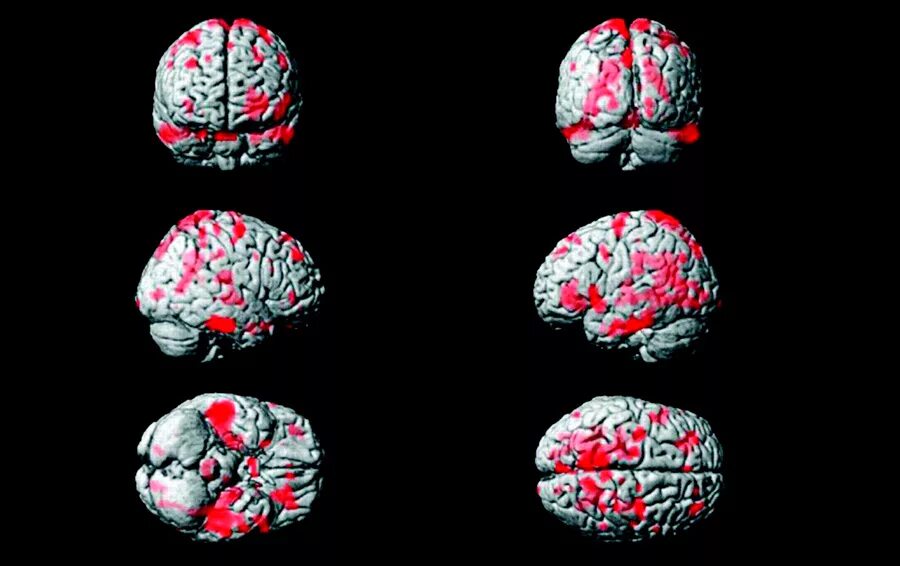

Диффузной биполушарной кортикальной атрофии